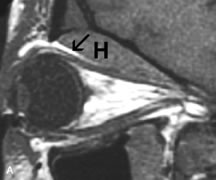

Tl relaxation time is the time required for the energized nuclei to give up the excess energy that was acquired from the RF pulse (high-energy state) and re-establish equilibrium (low-energy state) with the main magnetic field. The excess energy is released by these excited nuclei to the surrounding molecular environment, or lattice, and results in T1 relaxation, also called spin-lattice relaxation time. In different biologic tissues, hydrogen has a Tl ranging from a few hundred milliseconds to a couple of seconds. This range exists because local tissue factors affect the ability of specific protons to give up energy to the surrounding tissues. For example, hydrogen atoms attached to the carbon atoms of fat molecules relax much more rapidly than those attached to the oxygen atoms of water molecules. Viscosity, concentration, temperature, and molecular environment of the hydrogen atoms in the tissues also affect the T1 relaxation time. On a T1-weighted orbital image, fat, which has a very short T1 relaxation time, yields a high-intensity signal; the rectus muscles, which have an intermediate T1, yield an intermediate-intensity signal; and the vitreous, which has a long T1, yields a low-intensity signal (Fig. 8).5,8,16

Application of a 90° RF pulse brings the excited nuclei into phase so that the net vector of their magnetic moments is directed perpendicular to the static magnetic field. Shortly thereafter, the magnetic moments of the nuclei spread out and point in different directions, leading to a loss of phase coherence and a resultant decay in signal intensity amplitude. The T2, or spin-spin relaxation time, is the rate of decrease in the signal of these excited nuclei as a result of the interaction and transfer of energy to unexcited adjacent nuclei. T2 ranges from a few milliseconds to a few hundred milliseconds and, for a given tissue, is always less than the Tl relaxation time. T2-weighted orbital images are easily recognized by a high-intensity signal from the vitreous (Fig. 9).5,8,16